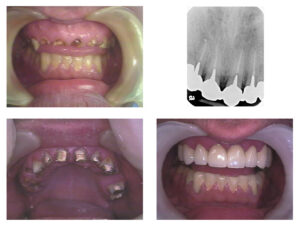

If you are looking for All-on-4 dental implants in Hyderabad, Infinite Smiles Multispeciality Dentistry in Banjara Hills offers this life-changing full-arch restoration under the expert care of Dr. Suleiman Talha, Principal Dentist and Implantologist. All-on-4 implants are a revolutionary solution for patients who have lost most or all of their teeth and want a permanent, natural-looking smile restored in a single procedure.

All-on-4 dental implants are a full-arch tooth replacement system that uses just four titanium implant posts to support an entire set of prosthetic teeth — upper, lower, or both. Unlike traditional dentures that rest on the gums, All-on-4 implants are anchored directly into the jawbone, providing stability, comfort, and function that closely mimics natural teeth.

The All-on-4 treatment at Infinite Smiles follows a structured, patient-centred protocol. It begins with a Consultation and Imaging session involving CBCT scan, dental photographs, and discussion of goals. This is followed by digital Treatment Planning using 3D software for precise implant positioning. On Surgery Day, four implants are placed under local anaesthesia, any failing teeth are extracted, and a temporary prosthesis is attached immediately — giving you functional teeth the same day. During the Healing Phase of 3–6 months, osseointegration occurs while you use the temporary teeth. Finally, the permanent zirconia or hybrid prosthesis is fabricated and fixed for the long term.

One of the key advantages of All-on-4 is that most patients walk out of surgery with functional teeth on the same day — often called Teeth in a Day.